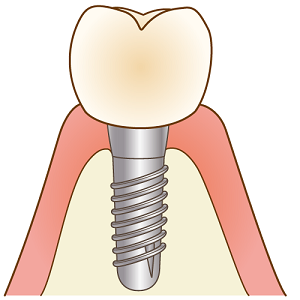

二次手術

インプラントの固定を確認し土台をつけるために歯茎に穴を開けます。

1週間ほどで歯茎が安定したら型を取ります。

歯の完成

かみ合わせを合わせたら歯を付けます。